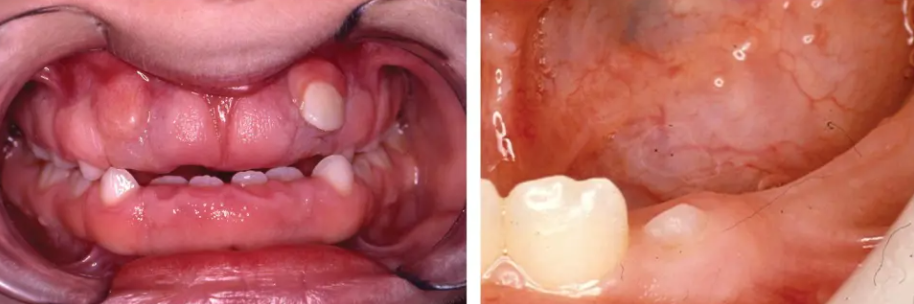

Ana, a mother of three from a coastal village in Visayas, noticed her youngest, Luis, wasn't getting his teeth like his older siblings did. By 15 months, he only had two tiny, discolored teeth. The local health center simply said he was "late bloomer." But Ana was worried.

Luis was fed primarily on lugaw (rice porridge) with a little salt, as fish and meat were expensive. Fruits were a rare treat. Ana’s husband was a fisherman with an inconsistent catch, and their income was unpredictable. Luis’s delayed teeth were a visible sign of an invisible problem—malnutrition. It wasn't until a medical mission visited their barangay that a volunteer dentist connected Luis's dental delay to a likely Vitamin D and calcium deficiency. The solution wasn't just about the teeth; it was about overhauling the family's diet with the limited resources they had.